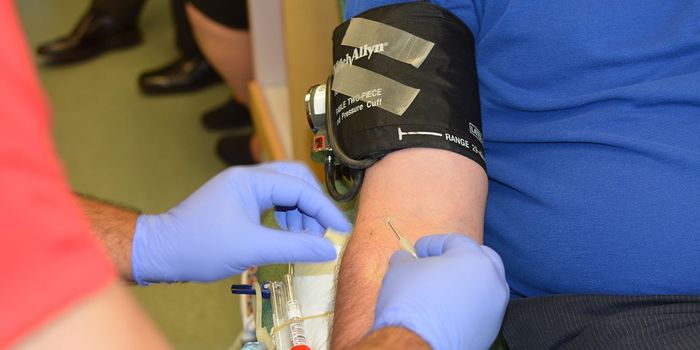

APR 14, 2018VideosExperiencing a little pain after being administered a shot, generally, is not something to be worried about. The pain is ...